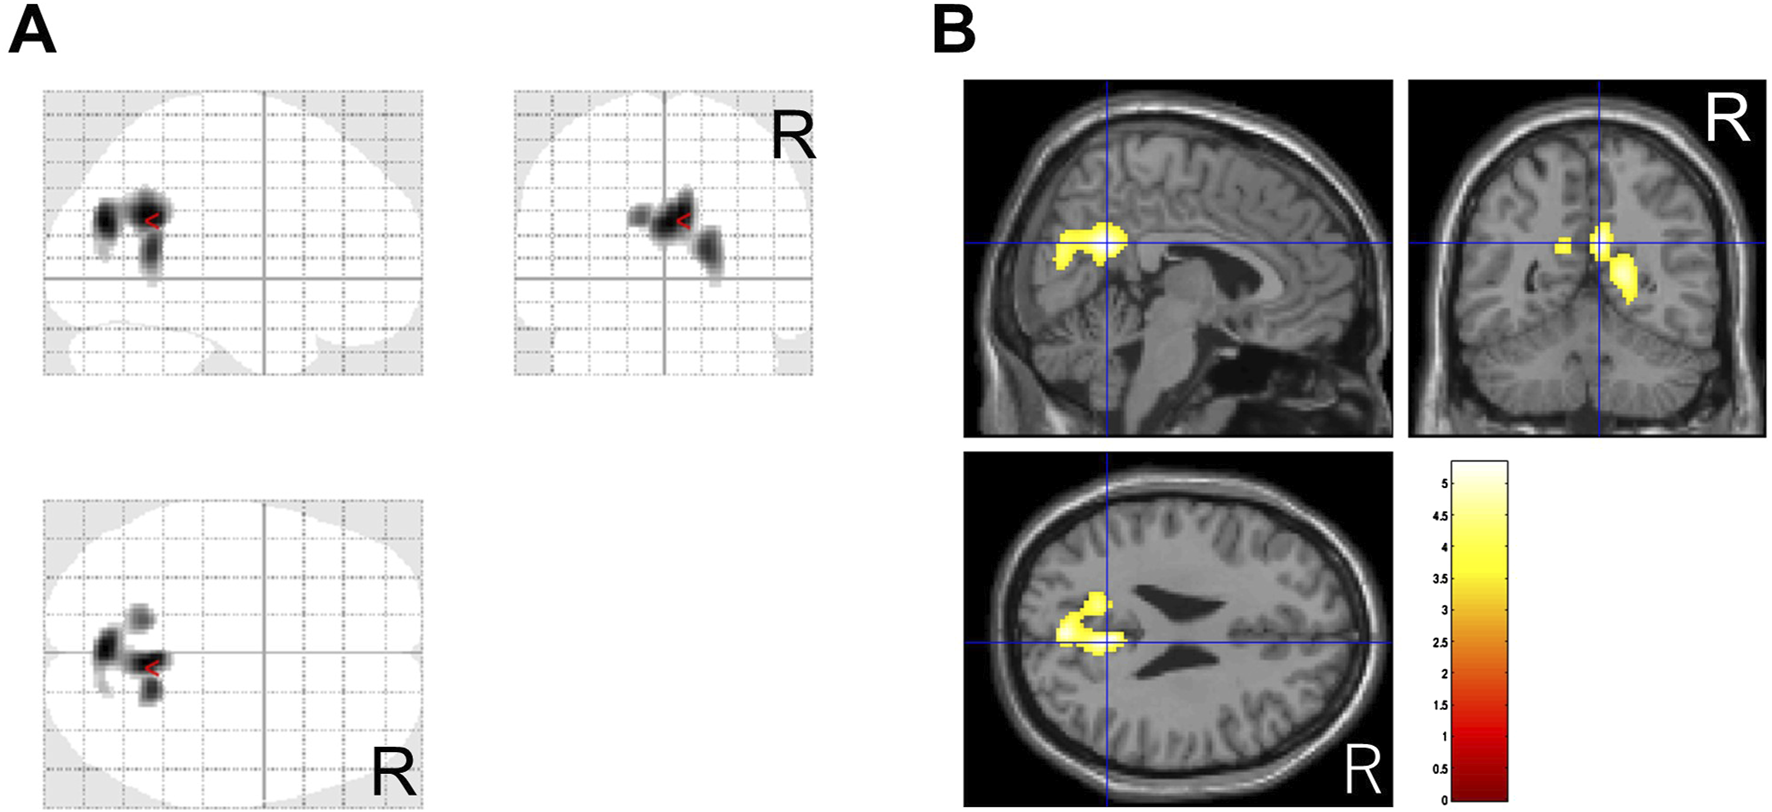

The duration of pre- and post-treatment CBF-SPECT was 32 ± 18 months, ranging from 7 to 74 months. Regarding the comparison of CBF-SPECT images before and after treatment in 61 patients with CGI-I scores of 1–3, the CBF was significantly higher in the precuneus, insular gyrus, and medial thalamus in pre-treatment CBF-SPECT images (Figure 2). No brain region showed significantly lower CBF in pre-treatment CBF-SPECT images and higher or lower CBF in post-treatment images.

Figure 2. Significantly higher cerebral blood flow regions in pre-treatment images than in post-treatment images. The regions with significant changes are projected in three directions in gray (A) and colored (t-value) scales with cross-bars indicating the precuneus (B) and right insular cortex (C). The medial thalamus is also identified as a higher cerebral blood flow region (C). Cluster-extent p < 0.05 with family-wise error correction. R, patients’ right side.

In this study, 37 patients were treated with MP or a combination of MP and other drug(s), and 36 of them had CGI-C scores of 1–3 after treatment. Before and after comparisons of CBF-SPECT images in these 36 MP-treated patients showed significantly higher precuneal perfusion in pre-treatment CBF-SPECT images (Figure 3).

Figure 3. Significantly higher cerebral blood flow regions before methylphenidate treatment than after treatment. The significant regions are projected in three directions in gray (A) and colored (t-value) scales with a cross-bar indicating the precuneus (B). Cluster-extent p < 0.05 with family-wise error correction. R, patients’ right side.